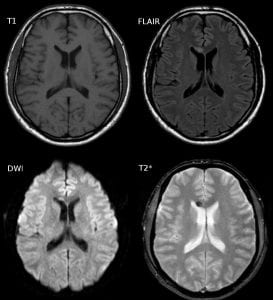

Diffuse axonal brain injury; image by Hellerhoff, via wikimedia.com, CC BY-SA 3.0, no changes.Diffuse axonal brain injury; image by Hellerhoff, via wikimedia.com, CC BY-SA 3.0, no changes.